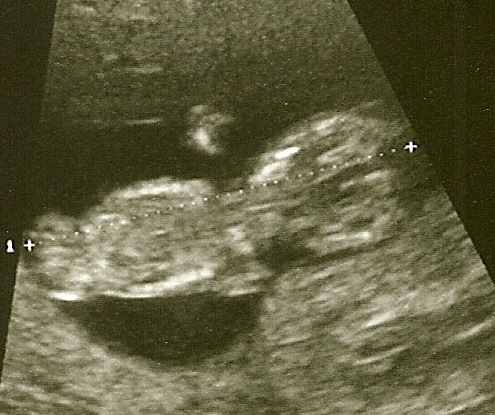

Я его видела! Не просто расплывчатую кривулину, а человечка с ручками и ножками, которыми он во всю уже шевелит )) Жалко конечно, что пока не рассмотреть мордашку, ну ничего, потерпим 2 месяца до 20 недель. Также как и полом.

Самое главное - сердцебиение 163, сильное и ровное, ну и ширина шейной складки 1,5 мм, это самая что ни на есть норма ))) Слава Богу. Теперь ждем анализов крови, но верю, что все будет хорошо. Под катом наш малыш )) Первые снимки. доступные обществу.